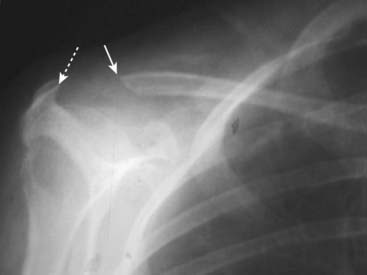

image

Figure 21-10 Avascular necrosis of humeral head.

There is increased density seen at the very top of the humeral head (solid black arrow) in this patient with sickle cell disease who developed avascular necrosis of the humeral head. Because the white cap on the bone looks like snow on a mountaintop, this sign of avascular necrosis has been called snow-capping.

Figure 21-15 Erosion of distal clavicle in hyperparathyroidism.

Another relatively common site of bone resorption in hyperparathyroidism is the distal end of the clavicle. Here the distal clavicle (solid white arrow), which should articulate with the acromion (dotted white arrow), has been resorbed, increasing the distance between it and the acromion. Other sites of bone resorption might include the terminal phalanges as in Fig. 21-14, the lamina dura of the teeth and the medial aspect of the tibia, humerus, and femur.